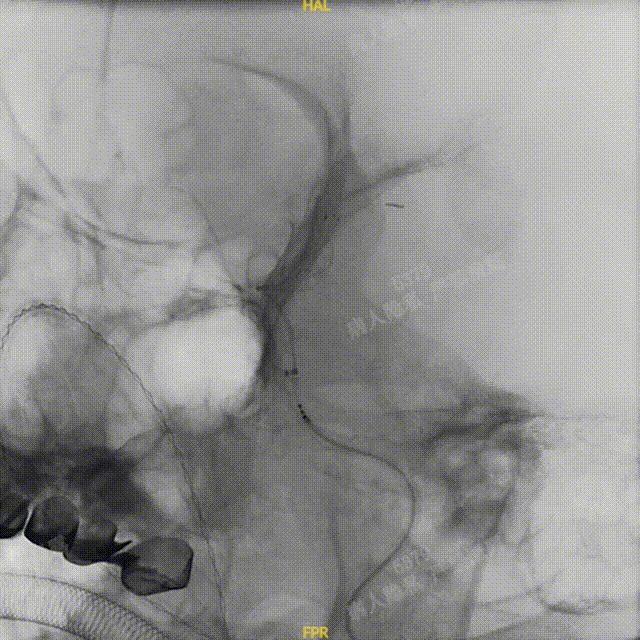

Headway™ 27 156cm微导管内输送FRED 5514血流导向密网支架,系统远端精准定位于预计着陆区以远2-3mm,回撤微导管原位释放支架,头端锚定在颈内眼动脉段。继续原位释放支架,注意保证微导管头端在释放过程中位于血管中央。

正位

①输送导丝头端

②支架远端显影点

③工作段螺旋显影丝

④支架近端显影点

完全释放FRED 5514血流导向密网支架,正、侧位造影及术后CT复查结果观察,载瘤动脉通畅、支架贴壁良好、动脉瘤内造影剂滞留、颅内未见明显异常。